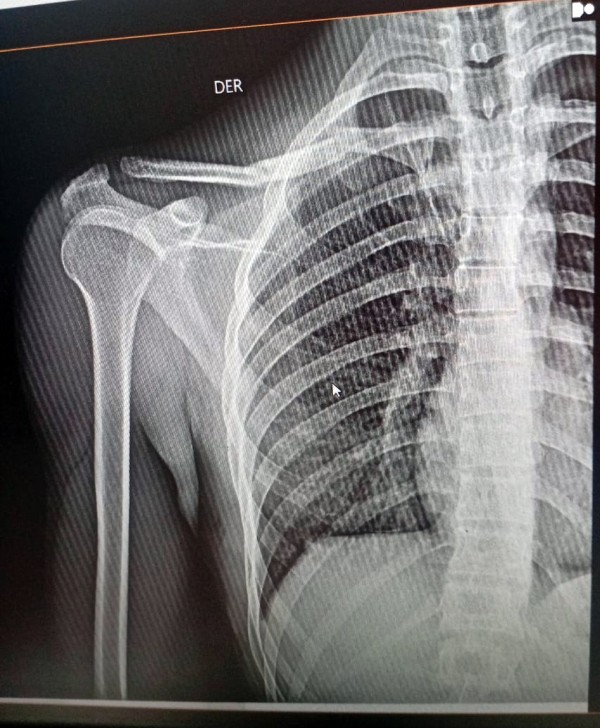

Una familia de barrio Raffo necesita de la solidaridad de todos. Tras un accidente vial ocurrido el sábado en Pilar, un joven rodriguense sufrió la fractura de su clavícula derecha en dos partes y debido a la difícil situación económica por la que atraviesan, se les hace imposible afrontar el valor de las placas anatómicas para que los huesos suelden correctamente.

Gustavo Molina Becker, de 20 años, estuvo internado hasta este lunes a mediodía en el hospital Vicente López y Planes. Ahora espera poder ser sometido a una intervención quirúrgica que le permita recuperar adecuadamente la zona afectada. La urgencia es que no puede pasar más de un mes o mes y medio porque si no, los huesos soldarían mal y los tendones se verían afectados por lo que perdería movilidad de su brazo, entre otros inconvenientes.

Gustavo precisa, de acuerdo a lo solicitado por el servicio de Cirugía Ortopédica y Traumatología del hospital, bajo el diagnóstico de Fractura segmentaria de clavícula derecha, realizarse una operación denominada Osteosíntesis de clavícula derecha.